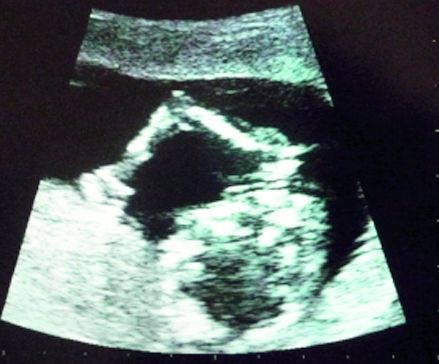

Raluca Zenga: Am declarat în repetate ocazii că 2009 este anul în care amândoi ne dorim apariţia unui micuţ în familia Zenga! Poate părea un eveniment comun, dar când ţi se întâmplă ţie… bucuria de a avea un bebe în pântece atinge proporţiile unui miracol divin!

E ca un boboc ce înfloreşte încet-încet! Cu cât se vede mai bine, cu atât mă simt mai mândră. Sunt atât de fermecată de noua “rotunjime”, încât atât eu, cât şi soţul meu “consumăm” burtica cu mângâieri, de multe ori inconştient chiar şi în public, pentru că e cel mai natural lucru cu putinţă!